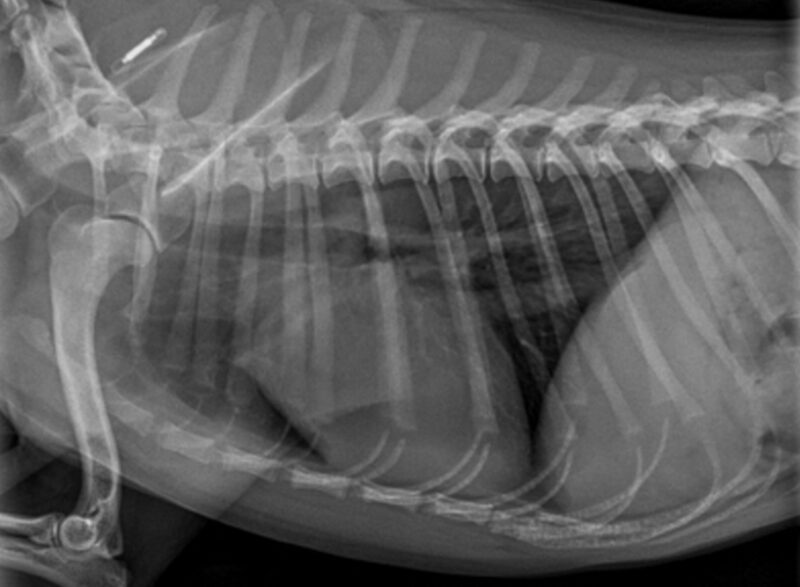

Vielen Dank für die Zusendung der Röntgenbilder. Uns liegt eine links laterale Aufnahme des Thorax vor. Hierbei ist die Herzschattenkontur, die Lungengefäße, das Lungenparenchym, die mediastinalen Strukturen, der Pleural Raum und die sichtbaren kranialen abdominalen Strukturen ohne besondere Befunde. Das Zwerchfell ist intakt und der abgebildete Bewegungsapparat ist normal, ohne Hinweis auf Frakturen.